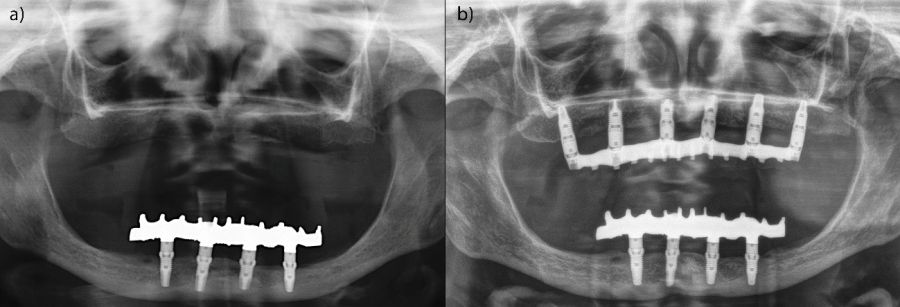

El análisis global de los 99 implantes reveló una pérdida ósea marginal media de 0,77 ± 0,26 mm en la superficie mesial y 0,79 ± 0,29 mm en la distal, valores que se mantuvieron dentro de los rangos considerados clínicamente aceptables para rehabilitaciones mandibulares. Cuando los implantes se categorizaron según su longitud, se observaron diferencias claras entre ambos grupos. Los implantes cortos (<10 mm) mostraron una pérdida ósea mesial media de 0,61 ± 0,23 mm y distal de 0,56 ± 0,22 mm, mientras que los implantes largos (≥10 mm) presentaron pérdidas significativamente mayores (mesial: 0,92 ± 0,19 mm; distal: 0,99 ± 0,17 mm). Dado que las pruebas de normalidad (Shapiro–Wilk) mostraron una distribución no normal en todos los grupos (p < 0,001), se aplicó la prueba no paramétrica de Mann–Whitney U. Los resultados confirmaron diferencias estadísticamente significativas tanto en la pérdida ósea mesial (U = 2068,5; p < 0,001) como en la distal (U = 2247,0; p < 0,005), indicando que los implantes cortos presentaron un comportamiento óseo más favorable que los implantes largos a lo largo del tiempo. Durante el tiempo de seguimiento que fue de media de 12,2 años (+/- 4,4; rango 6-23 años) no se objetivaron fracasos en ninguno de los implantes por lo que la supervivencia acumulada fue del 100%. El análisis del periodo de seguimiento mostró diferencias claras entre ambos grupos. Los implantes largos (≥10 mm) presentaron un tiempo medio de función de 14,1 ± 4,2 años (rango: 9–23 años), mientras que los implantes cortos (<10 mm) registraron un seguimiento significativamente menor, con una media de 9,8 ± 2,7 años (rango: 6–15 años). En las Figuras 3- 10 se muestran dos casos incluidos en el estudio, uno de cada situación descrita.